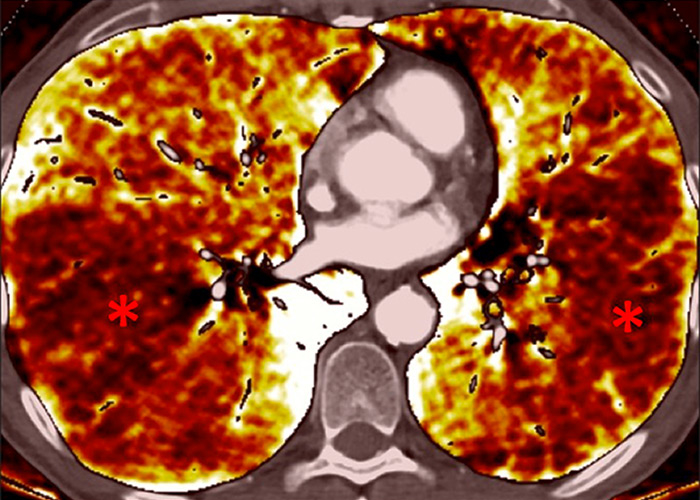

Figure 6

Perfusion heterogeneities in idiopathic pulmonary artery hypertension (stars) in two different patients (A/B). The dilatation of the arteries in pulmonary hypertension (arrows) is not always observed depending on the severity of pulmonary hypertension.